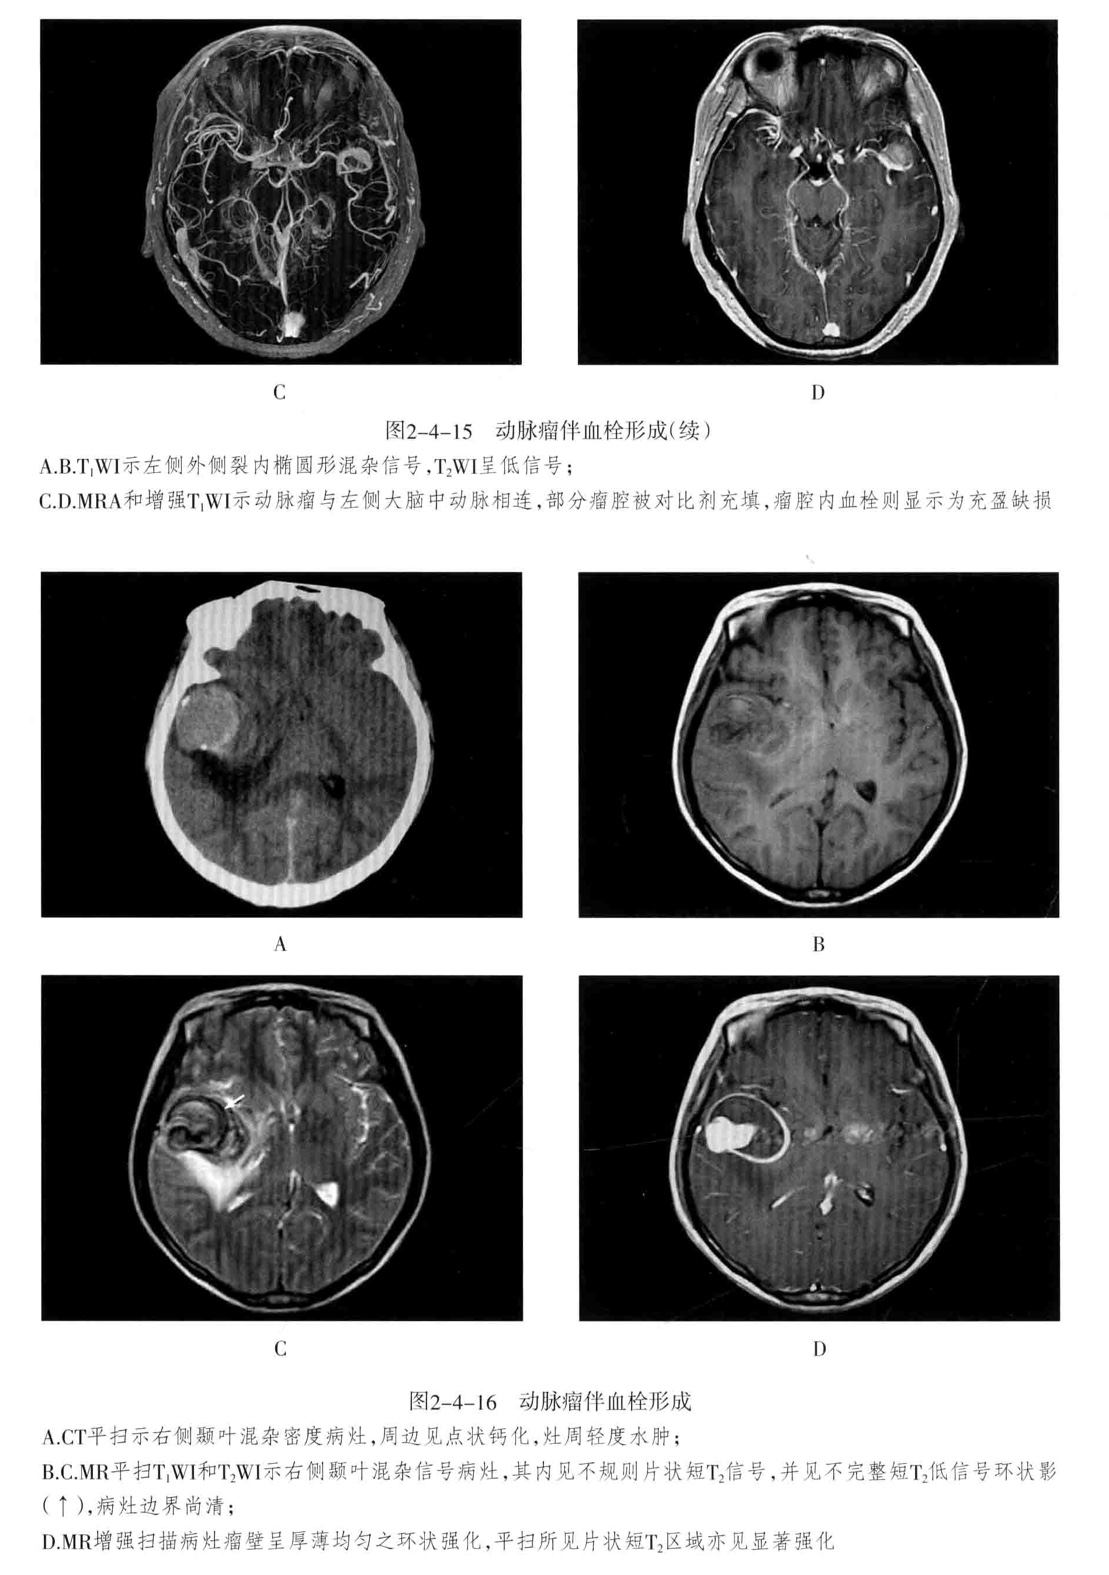

三、颅内动脉瘤

定义:颅内动脉局灶性异常扩大。

1. CT平扫为圆形高密度影,边缘清楚、增强有均匀强化,CTA或MRA可明确显示动脉瘤及其与载瘤动脉的关系。瘤样凸起。

2. 动脉瘤的瘤腔在T1WI、T2WI上均呈低信号,动脉瘤内有涡流时,也可产生轻微的不均质信号;瘤内血栓显示为高低相间的混杂信号。